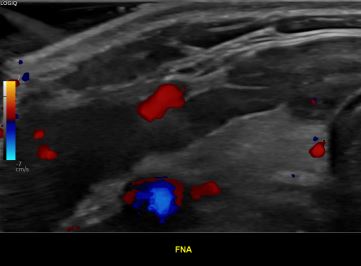

상기환자 외부건진이상소견 추적관찰위해 내원하신 30대중반 여성분으로

의심스러운 갑상선 협부 결절 세포검사 진행후 갑상선암으로 진단되었습니다